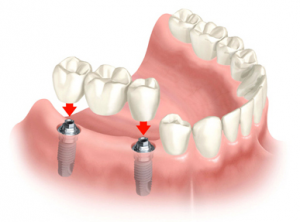

Эти конструкции могут быть металлокерамическими или на основе диоксида циркония. Одиночные коронки применяются в том случае, когда необходимо восполнить утерю одного зуба. В это случае на один установленный имплантат фиксируется одна коронка. Мостовидные конструкции можно применять для замещения нескольких утраченных подряд стоящих зубов. В этой ситуации импланты устанавливаются не под каждый зуб, а с промежутками, выполняя роль опор для мостовидных несъемных протезов.